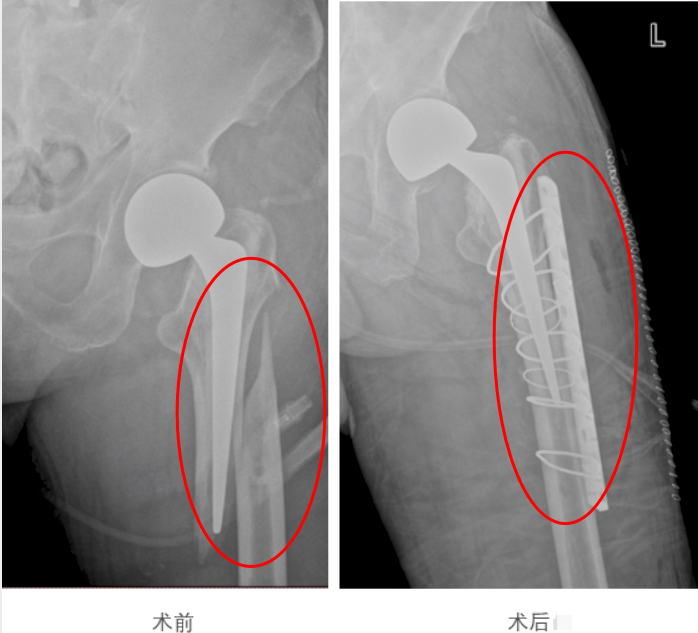

九旬老人廖伯(化名)做过左侧髋关节置换手术,没想到两周前在家中又不慎跌倒,到家附近医院住院,医生检查发现他左髋关节假体周围骨折。难怪廖伯痛得站不起来。更棘手的是,住院期间,他突然高烧至39.2℃,肺部感染迅速加重。情况危急!家人将他转入广州医科大学附属第一医院骨科求救。

在安全麻醉的保障下,赵亮主任带领团队,经外侧切口操作,避开血管神经丛,精准且迅速地为老人完成了骨折复位内固定手术。

手术顺利完成,术后该院多学科团队在精细化疼痛管理、个体化营养支持和循序渐进的早期康复活动等方面,为廖伯制定了加速康复计划——术后6小时,廖伯在医护人员指导下自主咳嗽排痰,进行呼吸训练;术后第二天,廖伯肺炎症状明显改善,能坐起身进食;术后第五天,老人家脱离吸氧,血红蛋白稳步回升;术后第七天,廖伯扶着助行器成功站起来了……